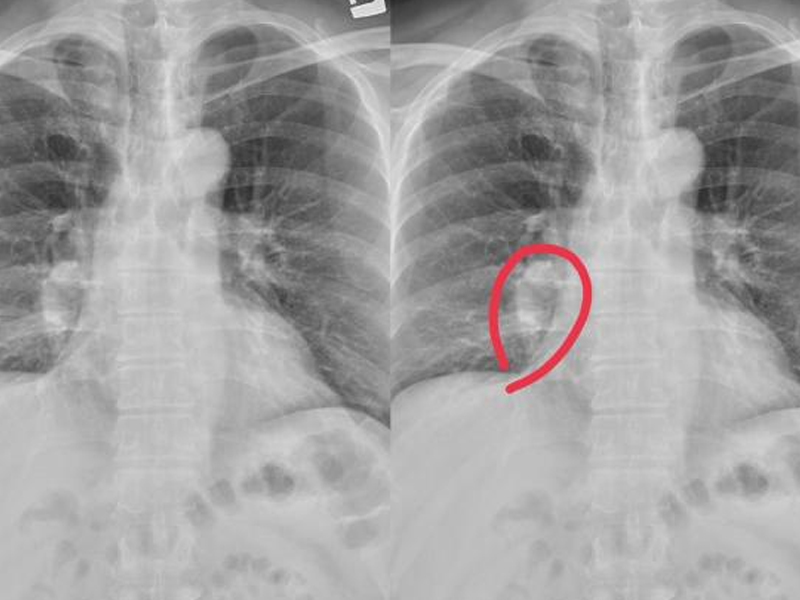

腿部有這 4 個症狀,高度懷疑是肺癌瀏覽:3993

肺癌仍然是發病率和死亡率最高的惡性腫瘤,尤其是男性。具體病因不是很清楚,一般認為是遺傳的,吸煙或觸摸二手煙和油煙、環境、心理因素和其他相關因素。提到肺癌,人們必定會想到乾咳、咳血、胸悶、呼吸短促等,但並非所有肺癌患者都會呈現這種症狀,這可能表現為雙腿。假如你的腿有以下症狀,你需求儘快去醫院做低劑量的胸部螺旋 CT 篩查肺癌。 1. 雙腿皮膚反常 中醫說:肺主要是皮毛,所以你能夠通過皮膚狀況來判斷肺功用是否傑出。肺是氣體交換的重要器官,但也能運送氧氣。在肺功用正常的前提下,血液中有滿足的氧氣。但在肺癌變後,必然會影響肺功用,使腿部缺氧,導致腿部皮膚白色或紫色。 2. 長痣 腿上的痣問題不大,但短時間內增長敏捷,尤其是直徑大於 2cm 時,伴有痣破裂、膿液、邊界不清,需求高度懷疑肺癌。  3. 腿部浮腫 長期坐着或站着.喝太多的水很容易導致腿部水腫,但只要積極的改進能夠緩解。假如腿部繼續水腫,按壓後反彈速度較慢,首先排除腎病,但也需求警惕肺癌。因為癌細胞的快速增殖速度,它能夠耗費體內的大部分能量,這很容易導致細胞浸透壓力失衡,使水逐漸浸透到細胞組織中。隨着癌細胞的擴散,它能夠壓榨下肢血管或神經,然後導致繼續的水腫,肺癌越嚴峻,水腫問題就越顯着。 4. 關節痛苦 許多肺癌患者在發病期間會呈現難以忍受的腿部痛苦,尤其是在行走時。因為癌細胞在增殖過程中能夠吸收肺部養分,也能夠轉移到其他部位。骨骼和關節首戰之地,因為骨骼中有豐富的血液和促進癌細胞生長的因素。 |